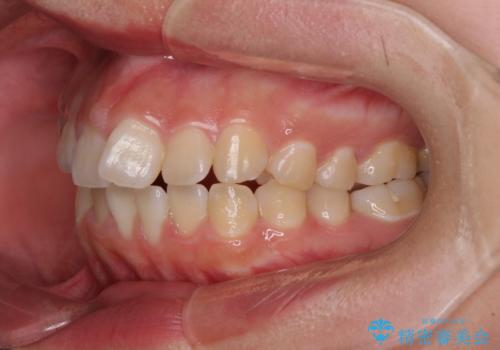

- 上下の前歯が非接触であることと、それに伴う口元の閉じにくさを気にして来院された患者様です。

奥歯の咬み合わせを見ると、上顎が下顎に対して相対的に前方にありました。

口元の閉じにくさを改善するためには、上顎臼歯を後方に移動させた咬み合わせにする必要があります。

インビザライン単体で改善することも可能ですが、達成する可能性が高くないため、カリエールディスタライザーという補助装置を併用して、より確実性を上げることとしました。

奥歯の咬み合わせを改善しながら、並行してインビザラインで歯列を整えることとしました。